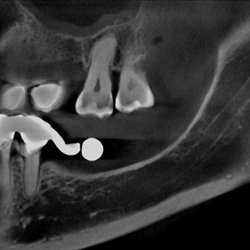

Mund-, Kiefer-, Gesichtschirurgie

• Lagebeziehungvon Weisheitszähnen zum Unterkiefernerv oder der Keilbeinhöhle

• Feststellung von Kieferhöhlenerkrankungen

Zahnärztliche Prothetik / Implantologie

• Planung implantologischer Versorgungen

• Exakte Positionierung von Implantaten